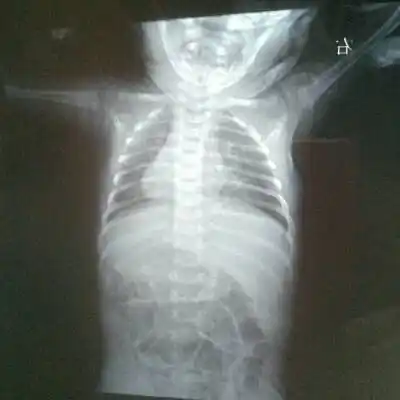

新生儿30天得肺炎,现在在妇幼icu,这是胸片,很严重吗